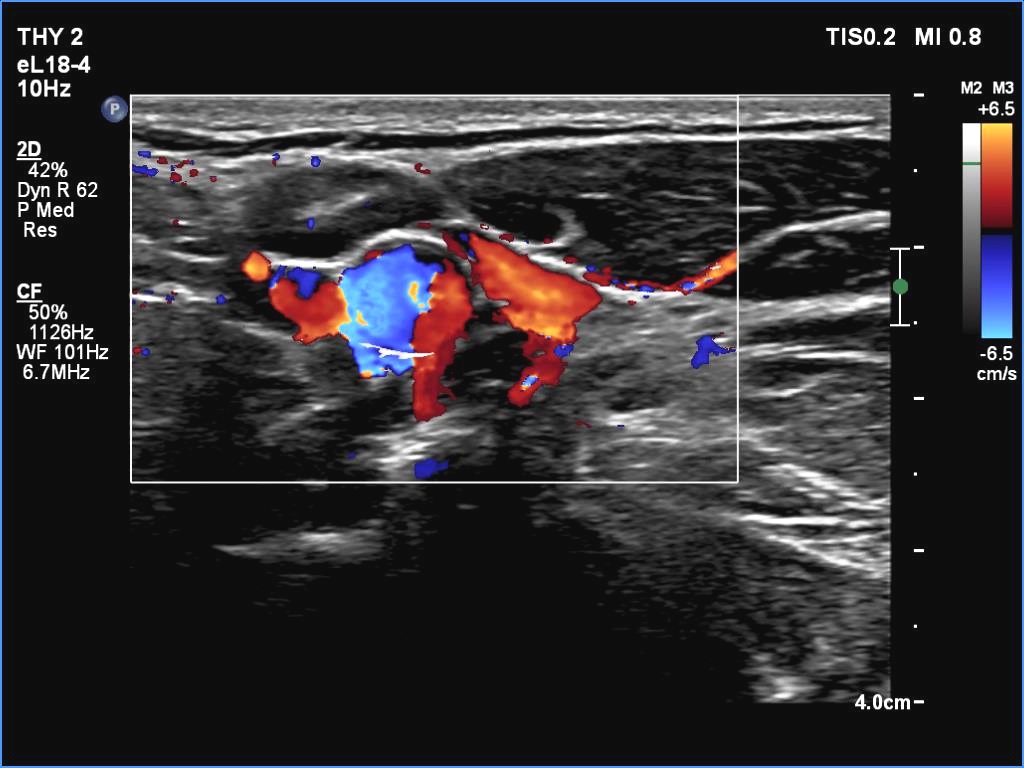

Left submandibular area, longitudinal scan, color Doppler mode. The vascularity is scanty.